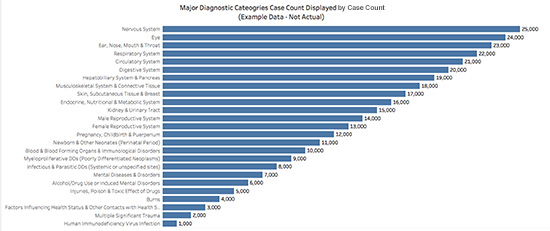

Enter the far less showy and oh-so-sensible, ever-practical bar chart. Displaying data using a bar chart affords us the ability to show the entire label for each value. Additionally, with the use of only one color, the viewer is no longer distracted by trying to understand what the different colors mean (nothing), and instead can see the shape of the data. It is also possible to directly label the value of each bar being displayed, and to rank the results or display them in some other potentially meaningful way, such as alphabetically by category.